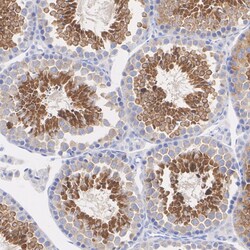

Positive Control: K-562 cell lysate, Jurkat cell lysate, HEK-293 cell lysate, COS-1 cell lysate, Mouse brain tissue lysate, Mouse testis tissue lysate, Rat testis tissue lysate, human testis tissue, mouse testis tissue, rat testis tissue.Tissue Specificity: Low tissue specificitySubcellular Location: Nucleus, Cytoplasm, Membrane, Mitochondrion.Sequence Similarities: 92% Mouse/RatPredicted band size: 49 kDa.

| Immunohistochemistry (Paraffin), Immunoprecipitation, Western Blot | |